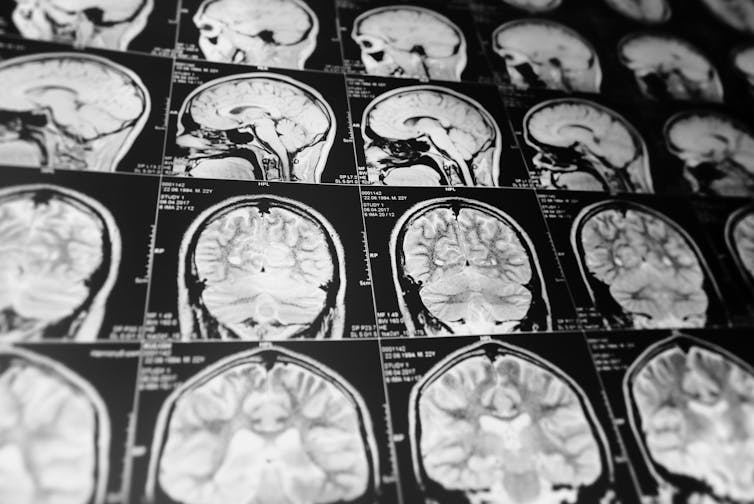

We screened the DNA and closely examined magnetic resonance imaging (MRI) scans from more than 70,000 people across 19 countries. We wanted to find out if there are specific genetic variants influencing differences in brain size between individuals.